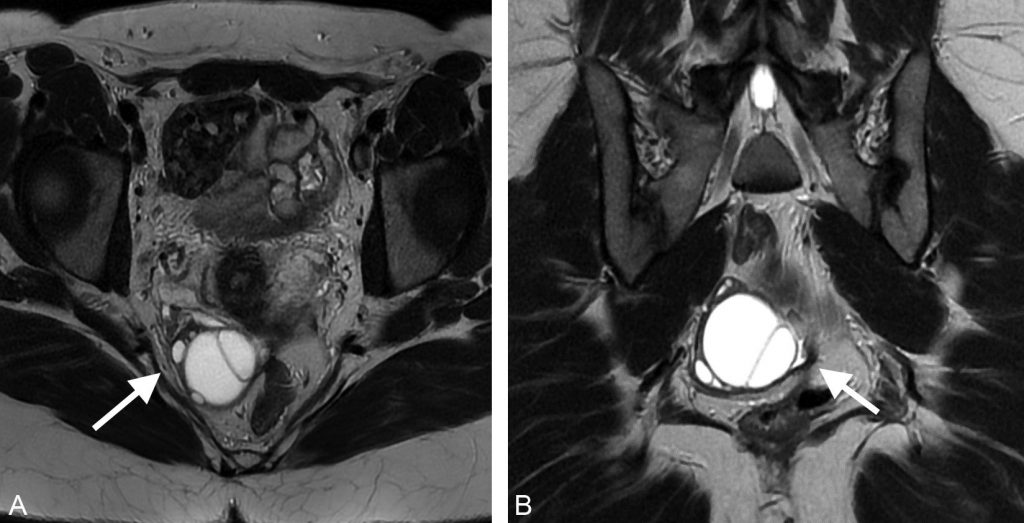

Fig. 20.3 Coupe axiale (A) et coronale (B) d’IRM pelvienne en séquence T2 chez une patiente de 28 ans présentant des douleurs pelviennes latéralisée à droite.

On retrouve une formation uniloculaire pure développée aux dépens de l’ovaire droit de paroi fine, en franc hypersignal T2 liquidien, sans végétation ni portion tissulaire, faisant évoquer fortement un kyste fonctionnel de l’ovaire.

Source : CERF, CNEBMN, 2022.